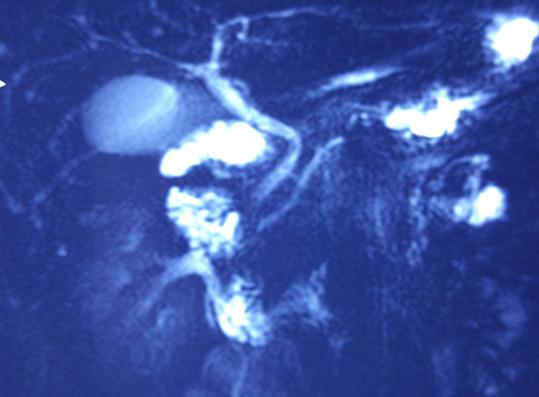

血管成像检查提示:脾动脉、脾静脉明显受压。

术前MRI: